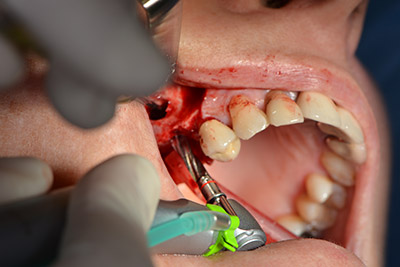

The classic incision (crestal, buccal relief) and the preparation of the mucoperiosteal flap enabled a good overview.

Sky implants (bredent) were used this case. The surgical protocol of these, specify pilot drilling at about 1200 rpm (Fig. 9).

The following holes were drilled at a reduced speed of 300 rpm. The Implantmed demonstrated its true capability at this stage. The surgical protocol can be preset – the various positions can be selected simply by pressing the “P” position of the foot control (Fig. 10 to 11).

Inclined drilling

Image 10: Inclined drilling to dorso-cranial at 300 rpm.